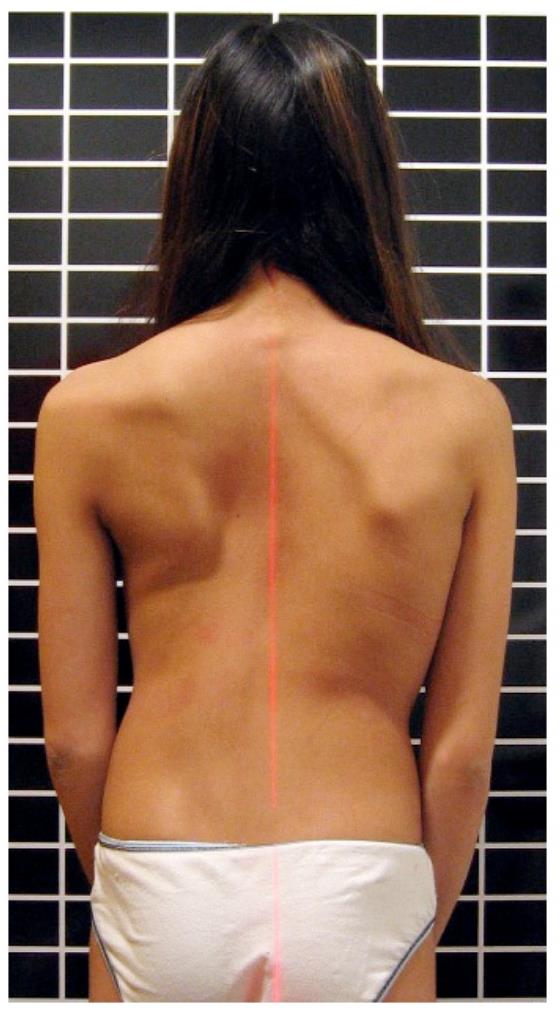

1. عدم تساوي الكتفين

إذا لاحظت أن أحد الكتفين أعلى من الآخر بشكل واضح، فقد يكون ذلك مؤشرًا على وجود انحناء في العمود الفقري.

2. بروز في أحد جانبي الظهر

عند انحناء الطفل للأمام، قد يظهر بروز في جهة واحدة من الظهر، وهو من العلامات المهمة التي تستدعي الانتباه.

3. ميل الجسم إلى جهة واحدة

إذا كان الطفل يقف أو يمشي وهو مائل إلى جانب معين، فقد يشير ذلك إلى وجود مشكلة في التوازن أو العمود الفقري.

4. اختلاف شكل الخصر أو القفص الصدري

اختلاف مستوى الخصر أو بروز أحد الجانبين أكثر من الآخر يشير إلى عدم التوازن العضلي أو وجود اعوجاج.

- اطلب من الطفل الوقوف بشكل مستقيم.

- اجعله ينحني للأمام ببطء.

- راقب الظهر من الخلف.

- بروز في جهة واحدة

- عدم تماثل واضح

- اختلاف مستوى الجانبين

- عدم تماثل واضح في الجسم

- ظهور بروز في جهة واحدة

- تقييم التماثل بين الجانبين

- اختبار الانحناء